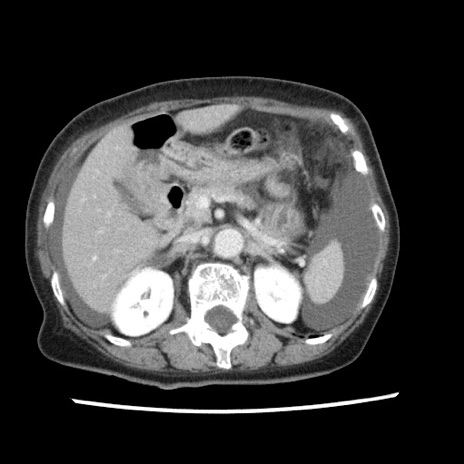

【症例】80歳代女性

【主訴】腹痛

【現病歴】8時間前から腹痛あり来院。

【既往歴】糖尿病、脂質異常症、子宮体癌にて子宮全摘術

【身体所見】意識清明・会話良好だが腹痛で苦悶様、全腹部にわたって反跳痛と圧痛あり

【データ】WBC 13600、CRP 0.14、LDH 224、CK 90